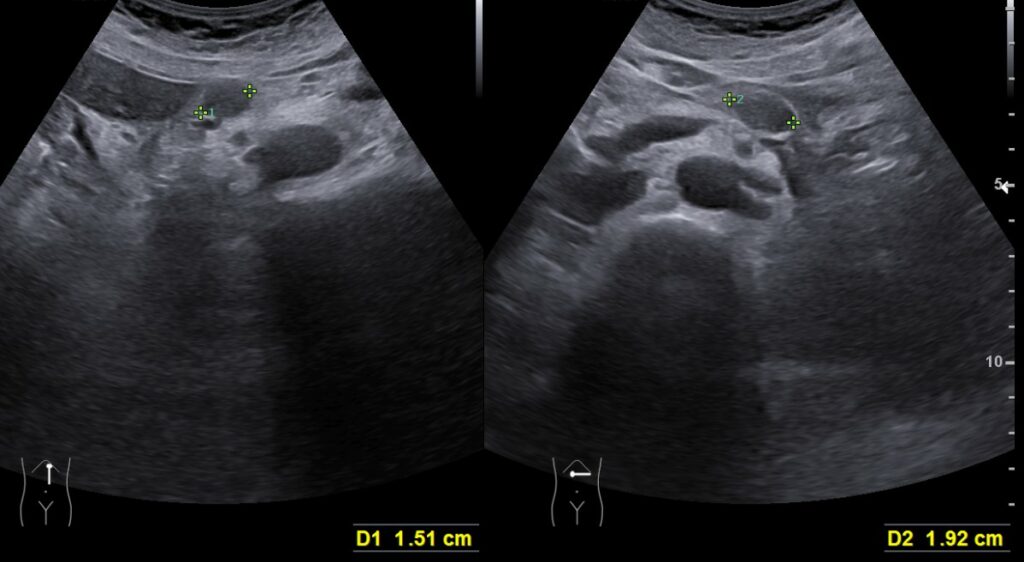

80대 남자, 옆구리가 아픈 증상으로 내원, 요로결석 진단

내원 전일부터 오른쪽 옆구리, 아랫배 부위 통증이...